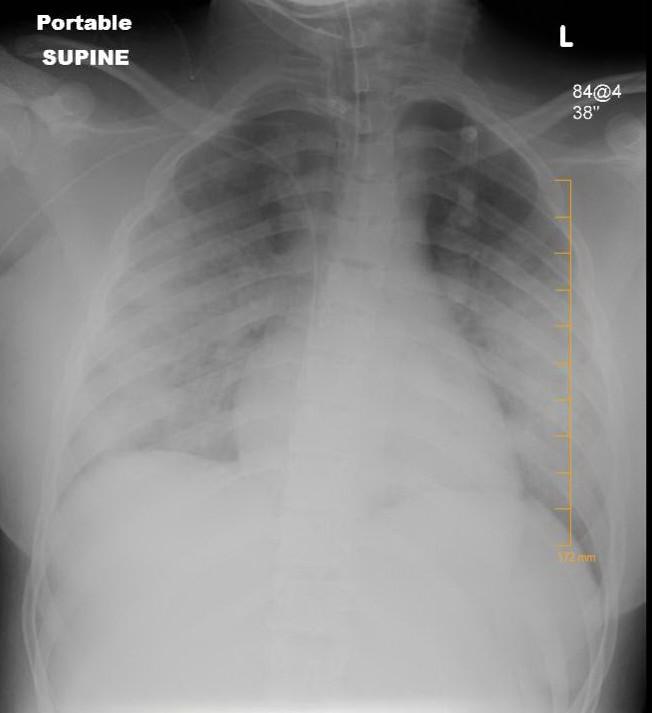

ARDS (IMAGE) Frontiers Caption X-ray of the chest of a patient with ARDS. Credit Courtesy Professor Kanwaljeet Anand Usage Restrictions This photo may be used freely with this article. License Licensed content Disclaimer: AAAS and EurekAlert! are not responsible for the accuracy of news releases posted to EurekAlert! by contributing institutions or for the use of any information through the EurekAlert system.